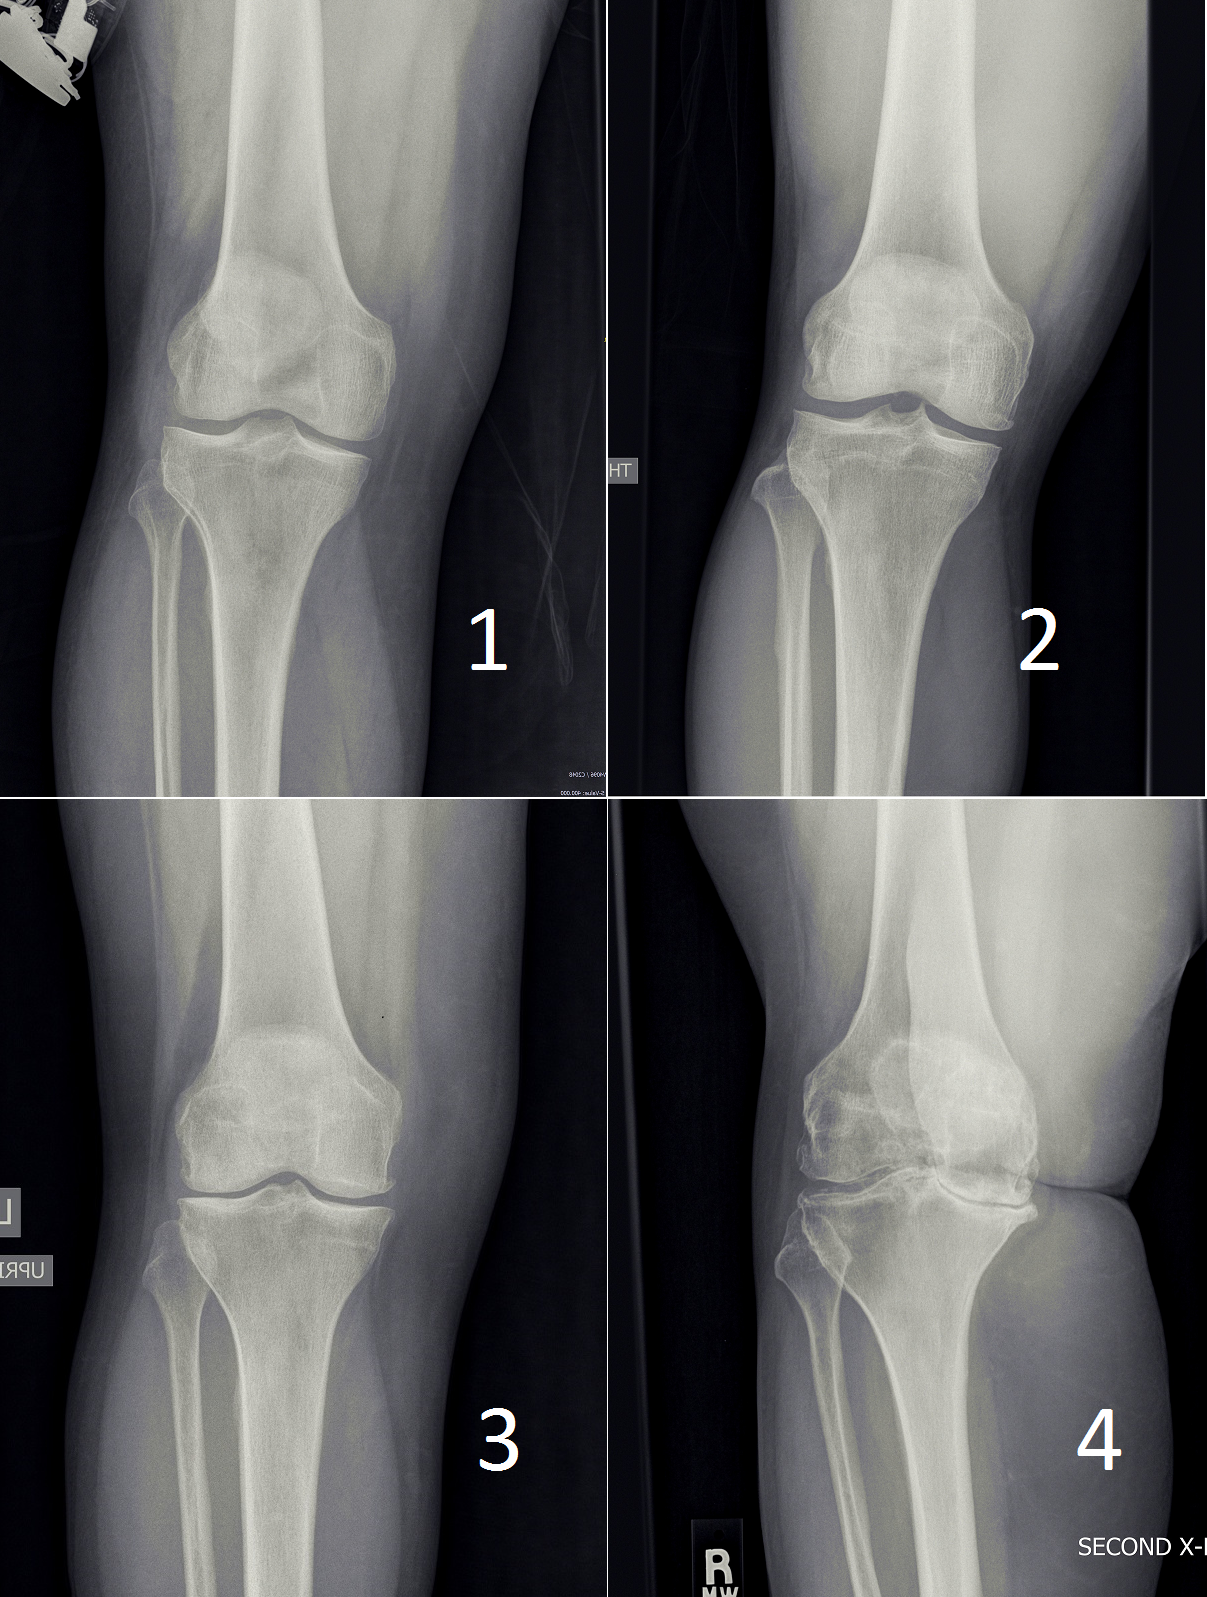

The following picture shows xrays of patients with different grades of arthritic disease. Grade 1, the mildest, has "doubtful" findings on xray. At the other end of the spectrum grade 4 has "bone-on-bone" disease, deformity, large osteophytes, and so on.

Before and after pictures of a knee replacement of a very arthritic knee that I treated with knee replacement.